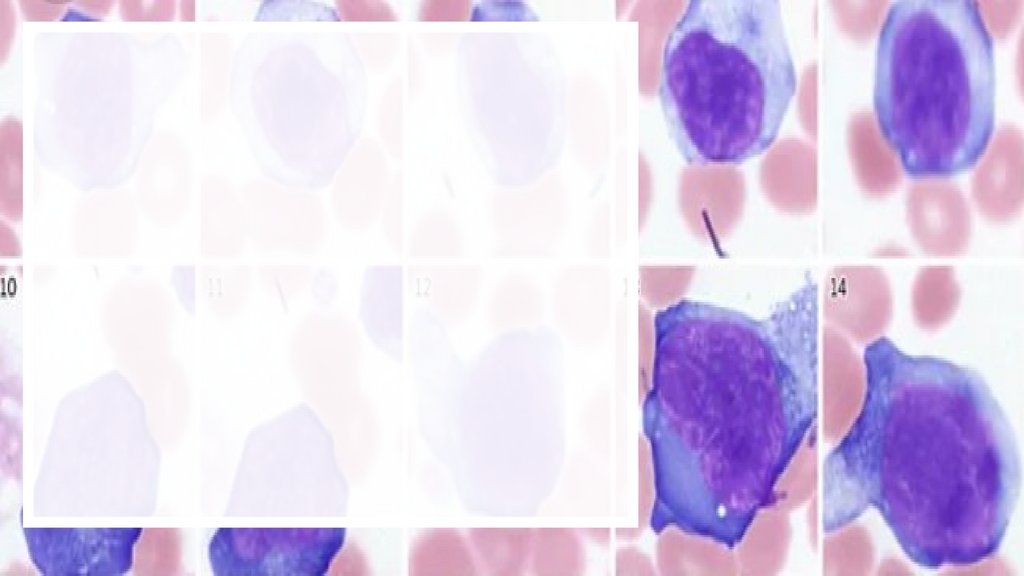

Лейкоциты

Лейкоци́ ты — неоднородная группа

различных по внешнему виду и функциям

клеток крови человека и животных,

выделенная по признакам наличия ядра и

отсутствия самостоятельной окраски.

Образуются в красном костном мозге,

обнаруживаются во всём организме

животного. Продолжительность жизни

лейкоцита колеблется от нескольких часов

до нескольких лет. Главная функция

лейкоцитов — защита организма

от патогенов и удаление продуктов

разрушения тканей.

Белые кровяные клетки

имеют цитоплазму и ядро.

Их подразделяют на две

большие

группы: зернистые

(гранулоциты) и

незернистые

(агранулоциты).

В цитоплазме

зернистых лей коцитов

содержатся зернышки

(гранулы), в цитоплазме

незернистых гранулы

отсутствуют.

Зернистые лейкоциты

В зависимости от окраски

гранул различают эозинофильные

(гранулы окрашиваются в розовый

цвет кислыми красками, например

эозином), базофильные (в синий

цвет основными красками) и

ней трофильные (теми и другими

красками в розово-фиолетовый

цвет).

У юных гранулоцитов ядро округлое,

у молодых оно в виде подковы

или палочки (палочкоядерные); по

мере развития ядро

перешнуровывается и разделяется

на несколько

сегментов. Сегментоядерные, или

полиморфно-ядерные, ней трофилы

составляют основную массу

гранулоцитов.

Незернистые лейкоциты

Они делятся на лимфоциты и моноциты.

Лимфоциты имеют крупное ядро, окруженное узким поясом

цитоплазмы. В зависимости от размера различают большие,

средние и малые лимфоциты. У лошадей и плотоядных

преобладают сегментоядерные ней трофилы —

ней трофильный профиль, у других - лимфоцитарный .

Моноциты — самые большие клетки крови, в основном

округлой формы, с хорошо выраженной цитоплазмой .